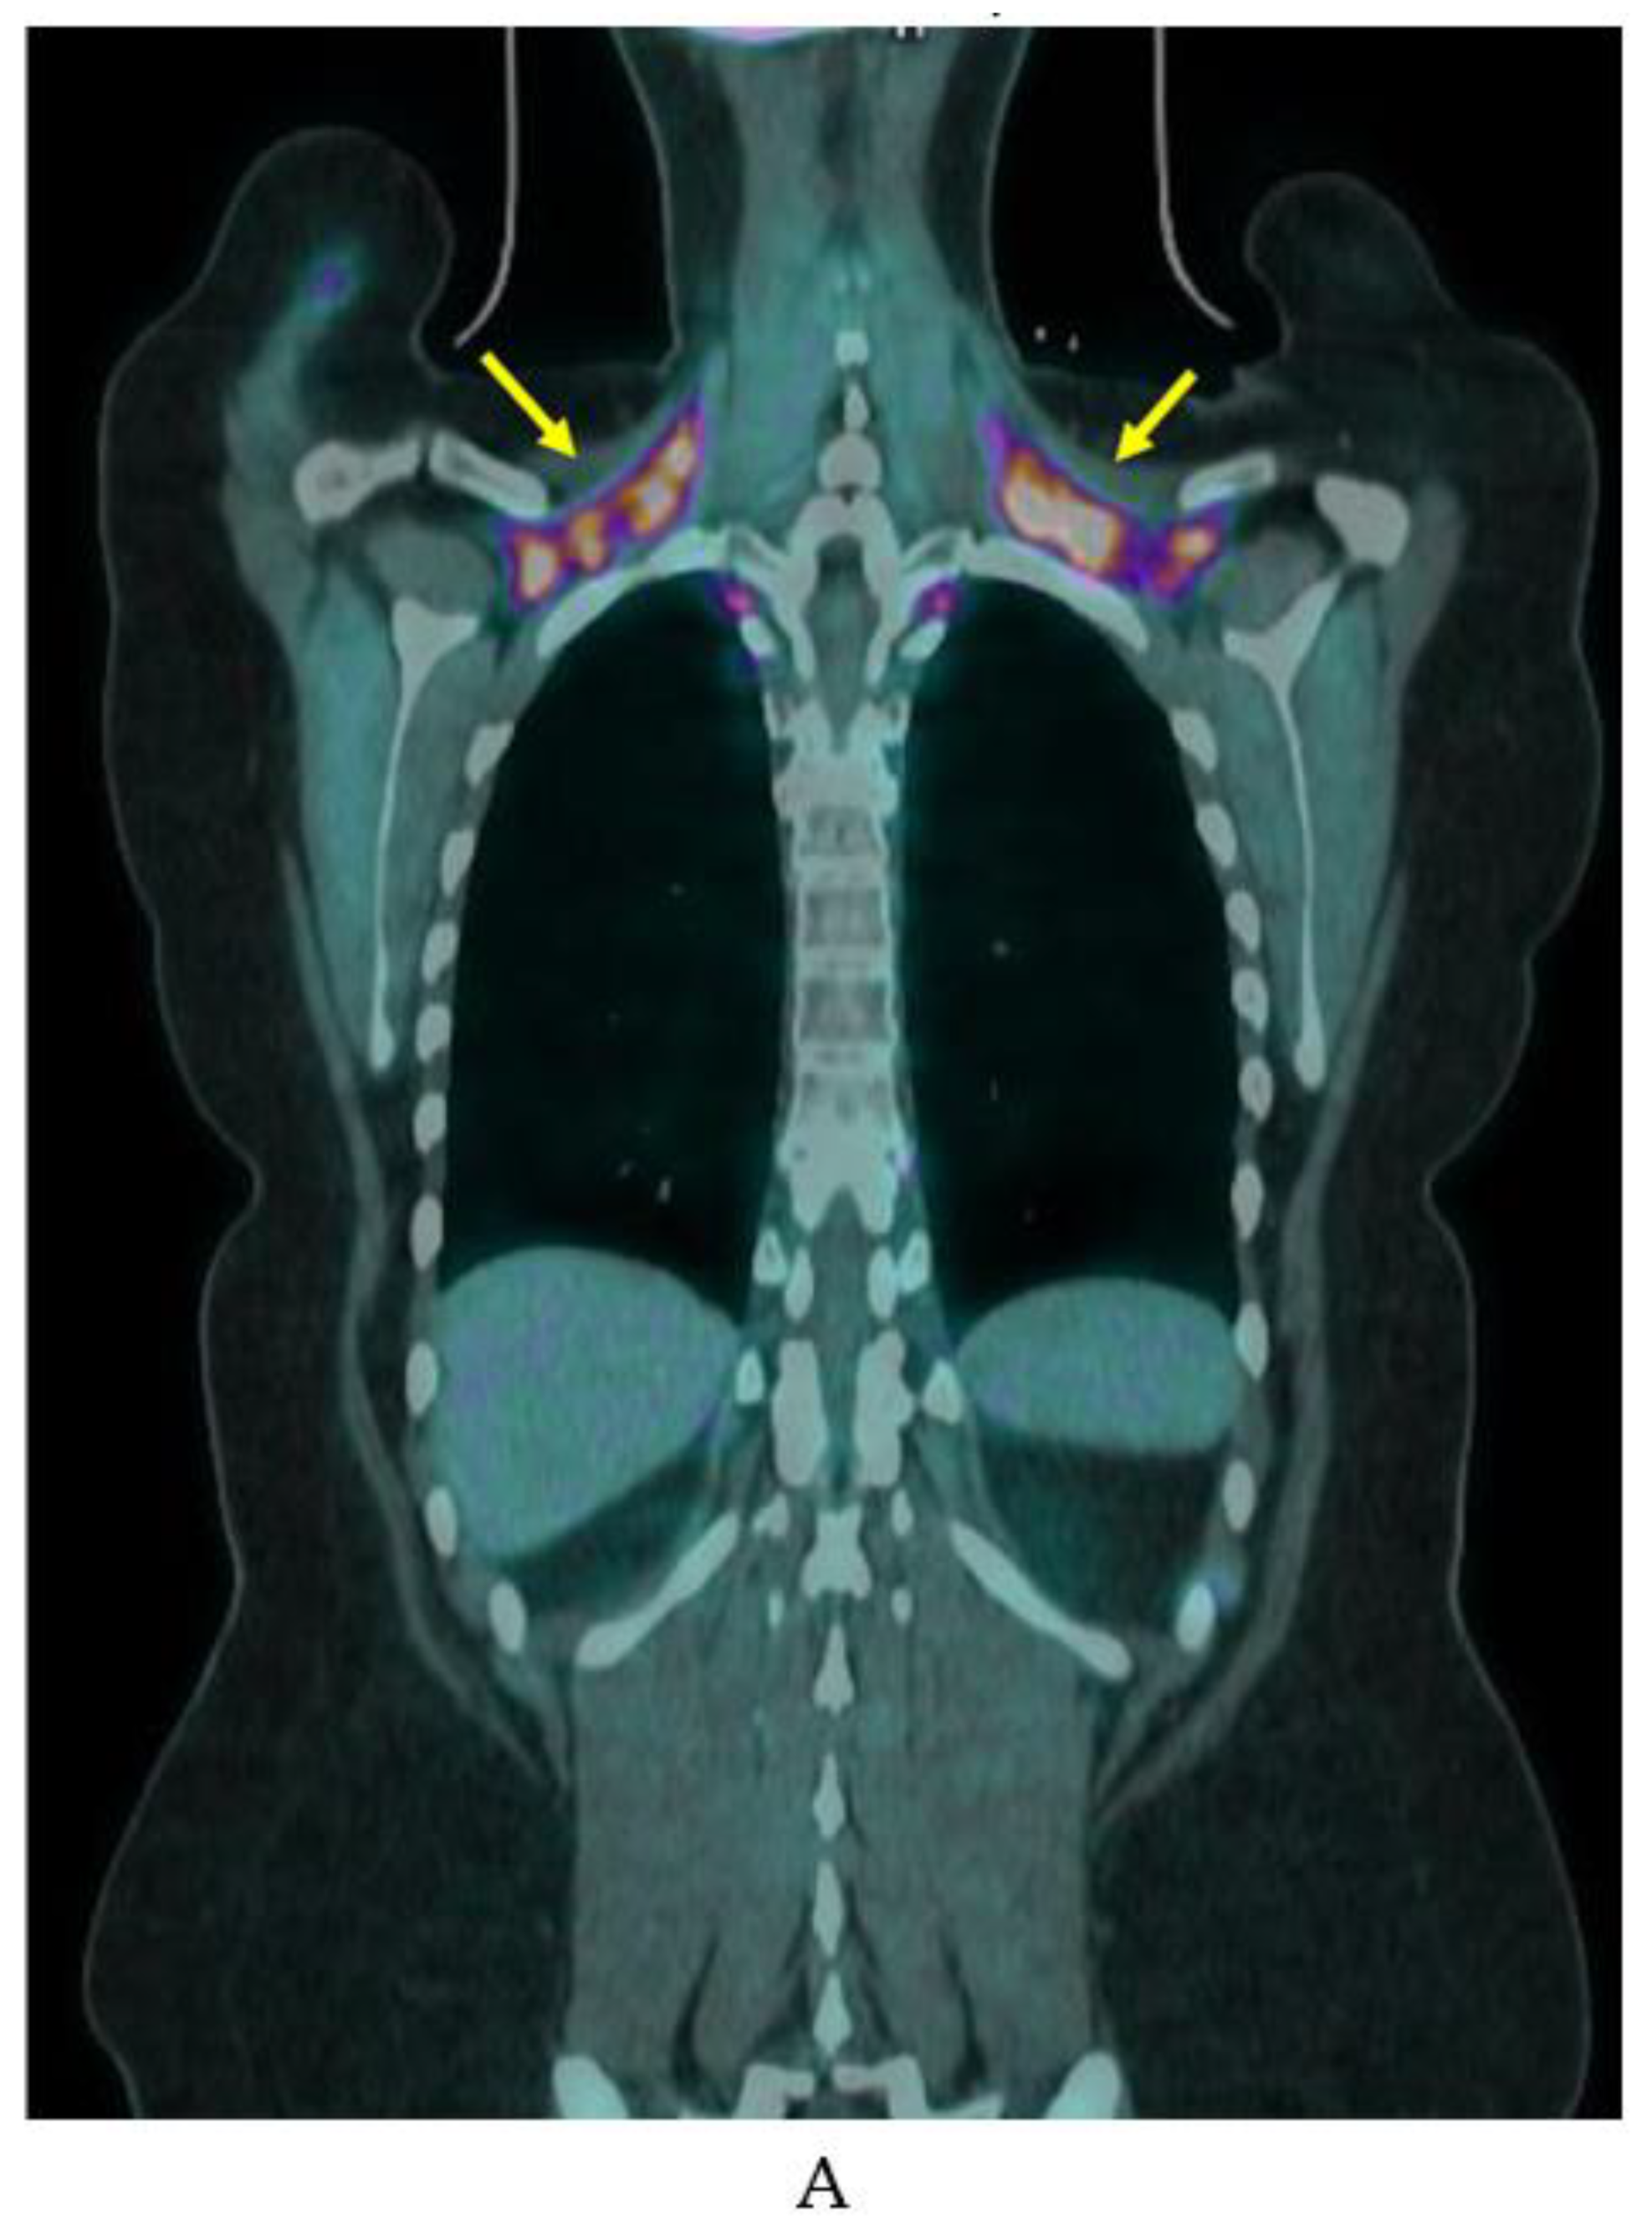

The rate of iBAT detected on a single FDG-PET/CT scan in large oncology cohorts is between 5–10% [14,16,53]. However, rate of detection rises substantially with repeated scanning or cold stimulation, although estimated prevalence varies widely between 20–100% [53,54,55]. Figure 5 shows an example of a patient with variably detectable iBAT. Indeed, seasonal changes in temperature impact iBAT prevalence estimates, limiting the utility of retrospective cohort studies [31]. Female gender and younger age have been associated with increased iBAT prevalence in large retrospective studies [15,56]. Lower adiposity, particularly visceral adiposity, is also associated with increased iBAT detection on FDG-PET/CT [15,57]. However, the lack of sensitivity to inactive BAT presents a problem to clinical BAT research as the most relevant subjects are obese and metabolically unhealthy.

Figure 5.

Example of variable iBAT uptake on FDG-PET/CT. FDG-PET/CT in a woman in her 20s showing marked BAT uptake in (A) November (yellow arrows) and no detectable BAT FDG uptake on a scan (B) 6 months later.